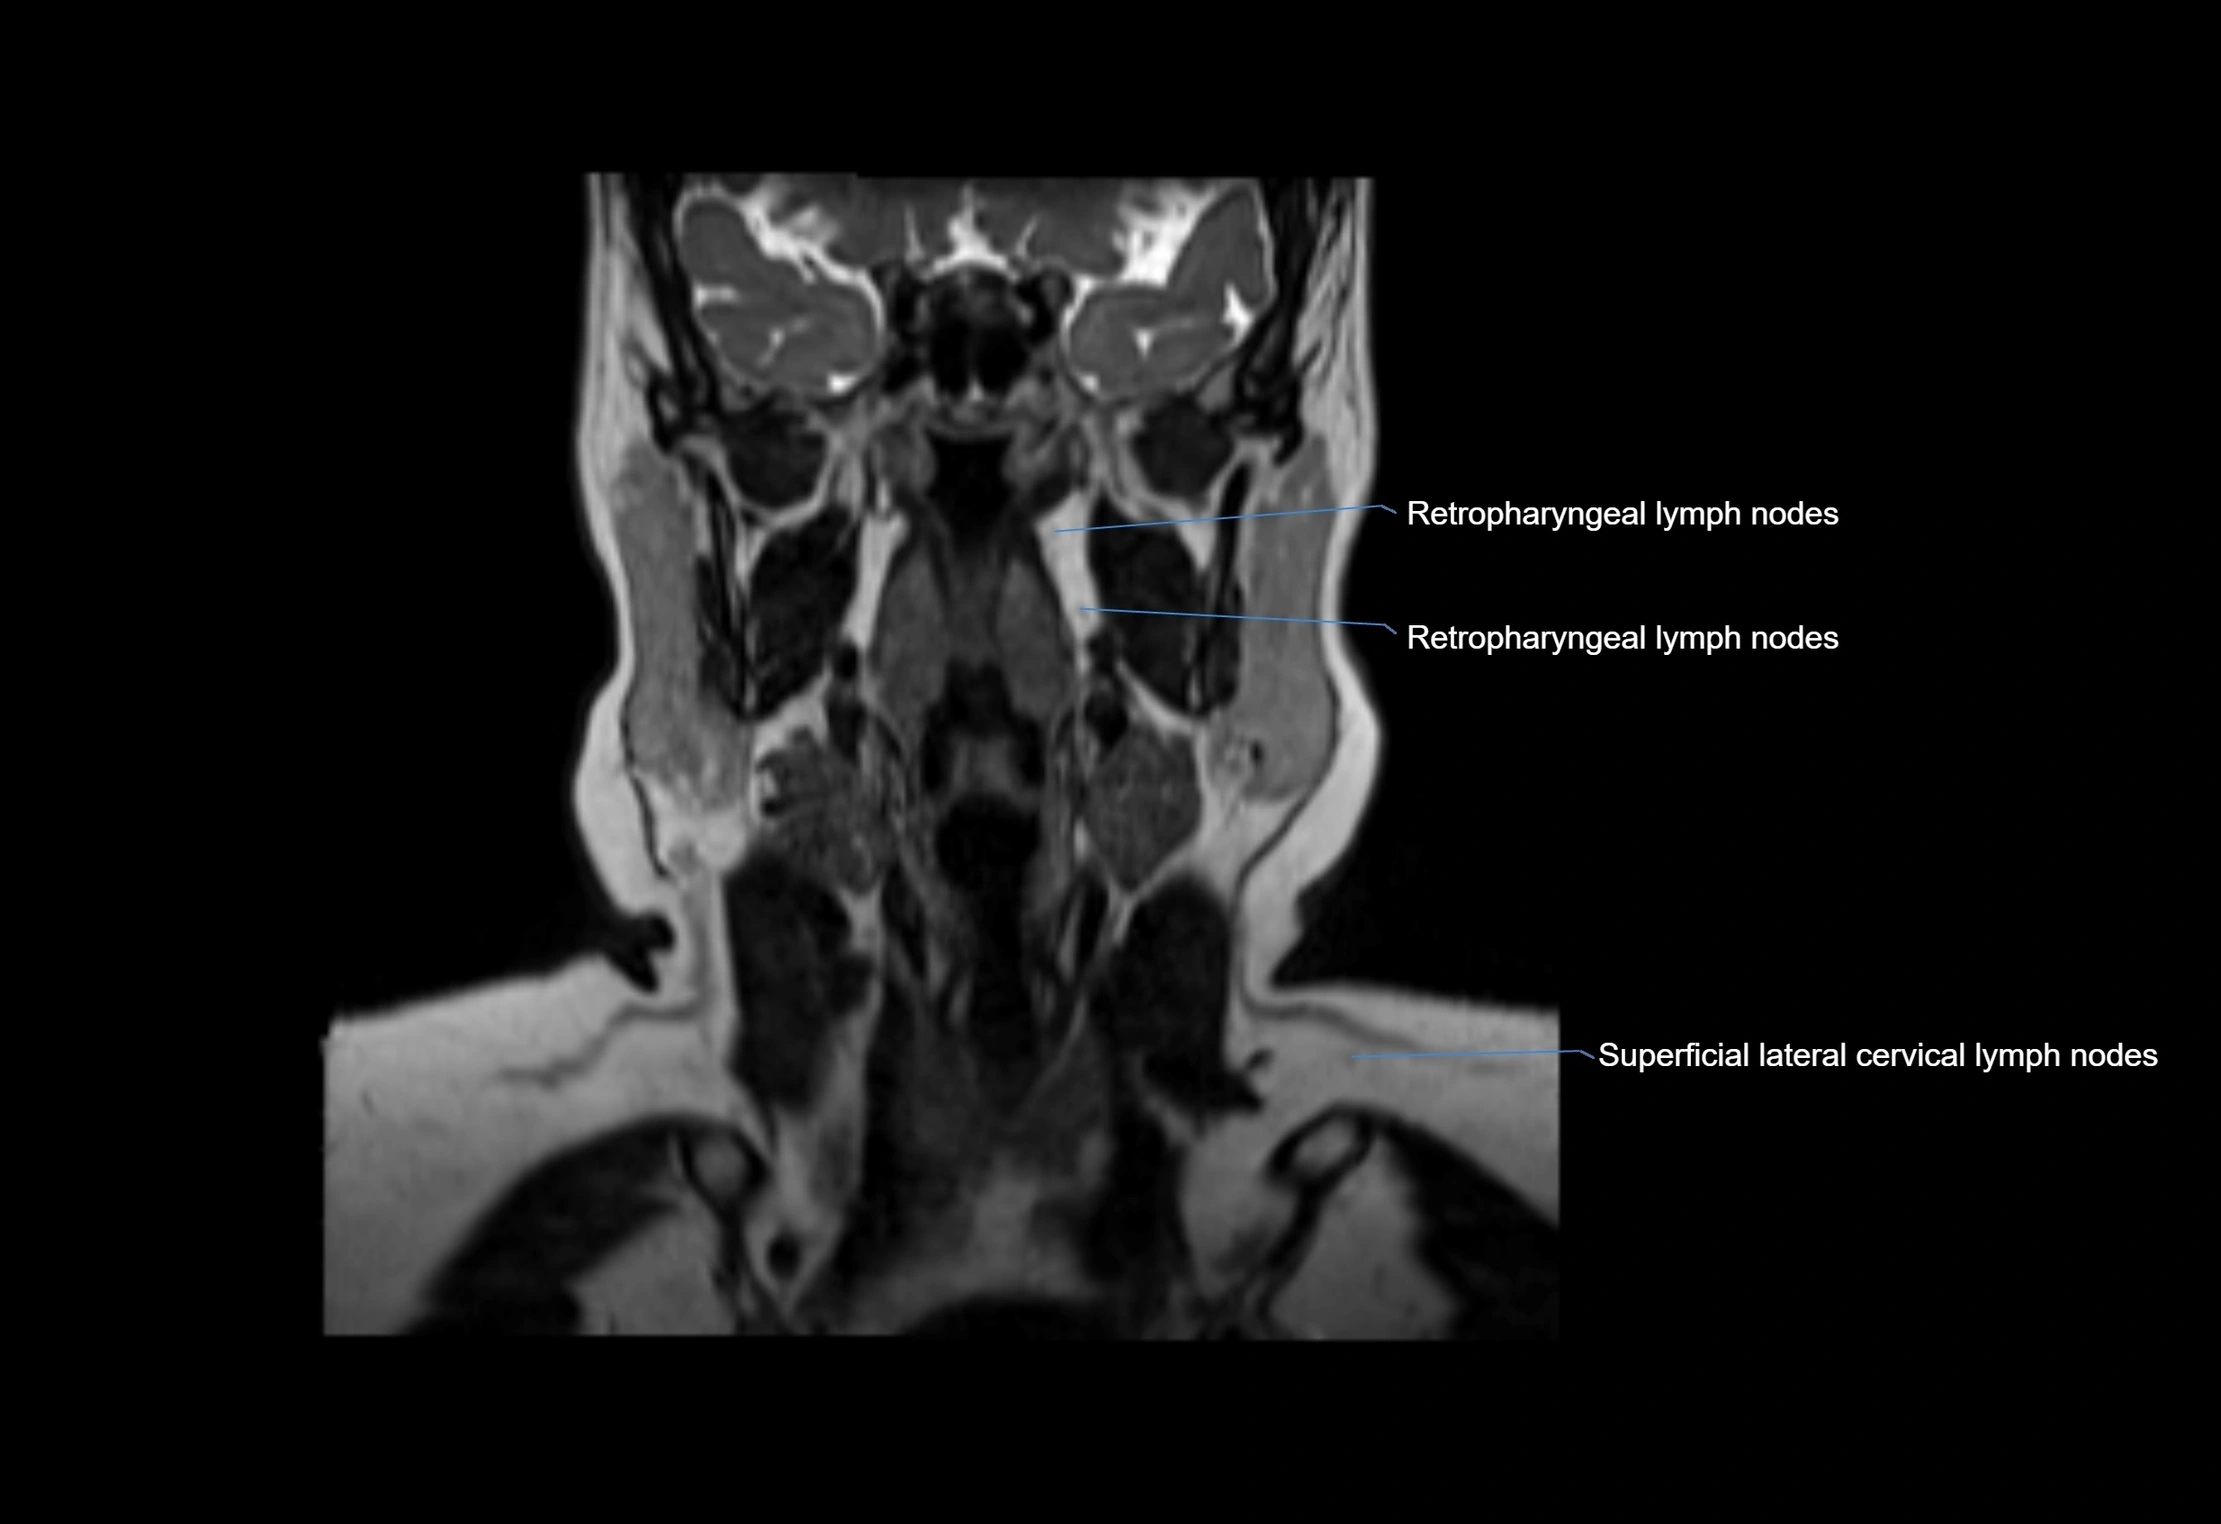

Accessory lymph nodes are small, secondary lymph nodes located along the main facial and cervical lymphatic chains, often adjacent to primary lymph nodes, such as preauricular, submandibular, or occipital nodes. They are typically less than 5 mm in diameter, embedded within subcutaneous fat or connective tissue, and may be variable in number and location. These nodes provide additional filtration and immune surveillance for lymph collected from the face, scalp, and neck regions. Accessory lymph nodes are usually non-palpable in healthy individuals but may enlarge in response to infection, inflammation, or metastasis, making them clinically significant.

Location

• Found along primary lymph node chains, including preauricular, submandibular, parotid, and occipital regions

• Embedded in subcutaneous fat or superficial fascia, often lateral or posterior to primary nodes

MRI Appearance

T1-weighted images:

• Normal accessory nodes appear as small, oval hypointense to intermediate signal structures within subcutaneous fat

• Surrounded by hyperintense fat, enhancing contrast for visualization

• Pathological nodes may appear enlarged or rounded, sometimes with cortical thickening

T2-weighted images:

• Nodes show intermediate signal, with surrounding fat bright

• Useful for detecting edema, inflammation, or infiltration

• Fatty hilum may appear slightly hyperintense relative to cortex

MRI images

image